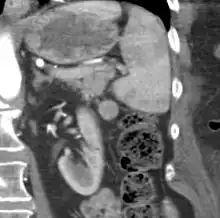

| CT scan of an accessory spleen (circular object in center of image) between the spleen and left kidney. | |

If splenectomy is performed for conditions in which blood cells are sequestered in the spleen, failure to remove accessory spleens may result in the failure of the condition to resolve.[1] During medical imaging, accessory spleens may be confused for enlarged lymph nodes or neoplastic growth in the tail of the pancreas,[5] gastrointestinal tract, adrenal glands or gonads.[2]